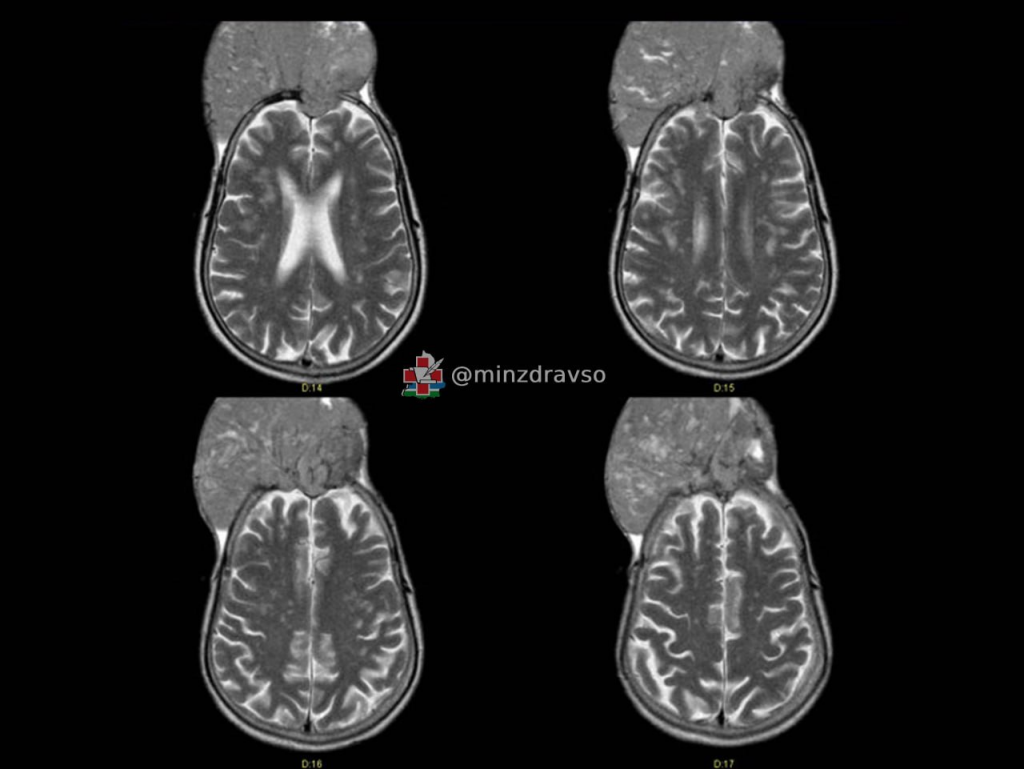

Так как такие опухоли питает обширная сосудистая сеть, хирурги сначала «закупорили» нужные сосуды, и лишь затем отделили менингиому от мозга. Позже пациенту сделали пластику оболочки и крупной вены, установили титановую сетку, протезирующую череп, выполнили пластику кожи и провели другие манипуляции для формирования анатомически правильной формы черепа. Операция длилась почти семь часов.